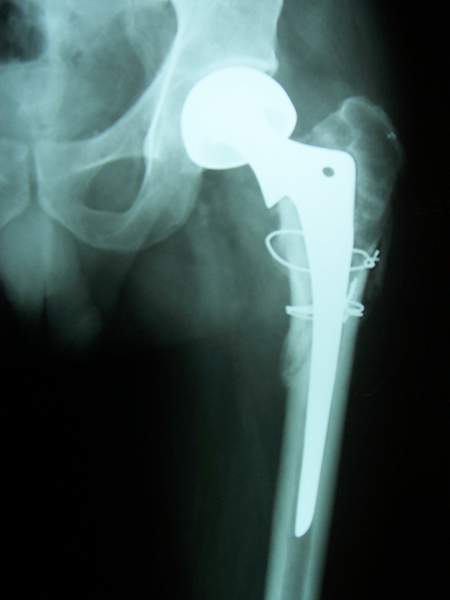

Case:7 Fracture Neck Femur with Implant failure and Re-Fixation with hemi-arthroplasty

Alcoholic Gardener by profession had slipped in bathroom & fell. He sustained fracture neck femur.He was operated with closed reduction & CC Screw fixation under IITV. Two weeks’ post fixation he again fell & sustained fracture in sub trochanteric region. He was treated with Hem-Arthroplasty with Tension band wiring.

Post-Op

Post Prosthesis Fall

Post Uninon-3Months